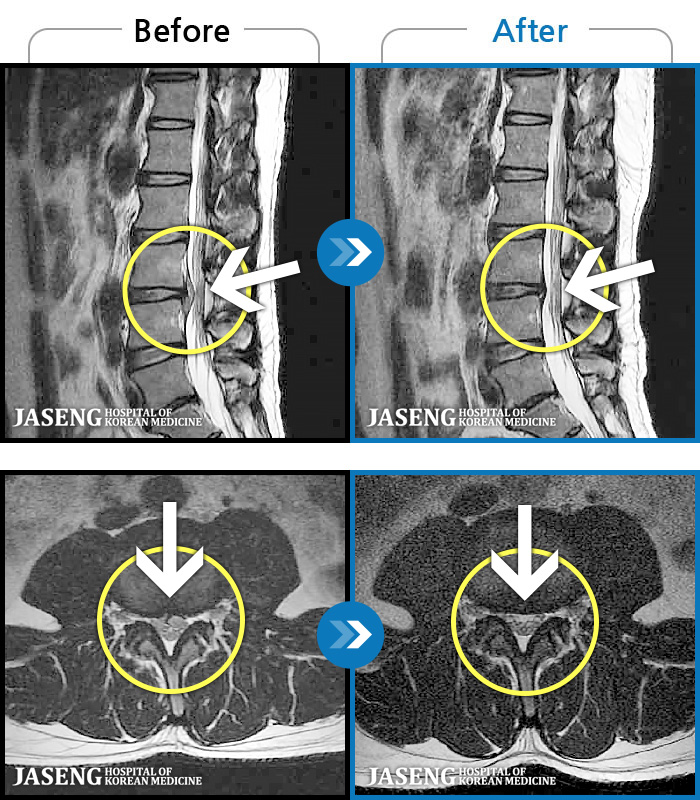

ó 㸮 , ٸ ϰ ־ Ȱ , ߰ ᵵ ڰ Ͽ Ȱ ¼̽ϴ. |